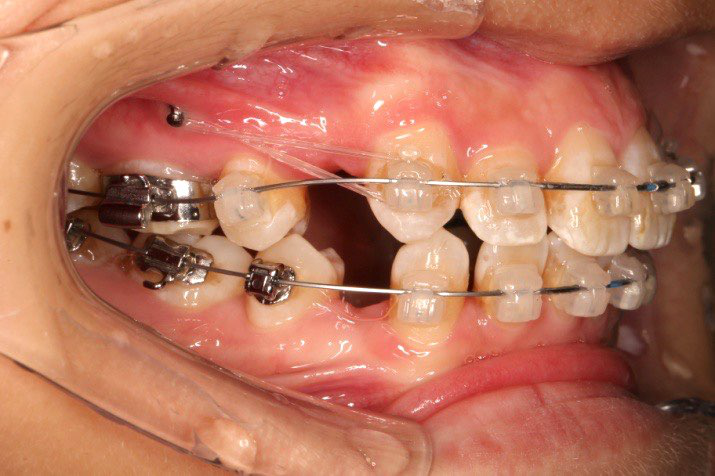

2018.5.25  (19个月)拆TPA,16、26粘tube 上颌0.14*25cu-niti  下颌0.018*25niti2018.7.23  上颌 0.017*25TMA,下颌0.017*25ss43压低曲,双侧后牙垂直牵引

2018.09.29  15、43、16、17、11、21重粘,上0.016*25cu-niti 下0.018niti 上连扎

2018.11.14  术后侧面改善明显,露龈笑改善明显,笑弧笑线协调,颏部肌肉紧张度明显改善

2018.11.14  术后磨牙尖牙I类关系,中线齐,覆合,覆盖正常